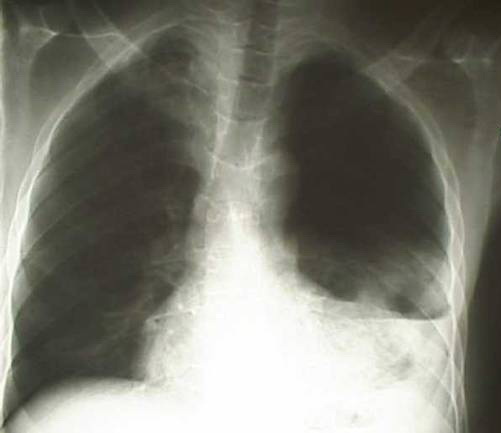

Клиника зависит от интенсивности внутреннего кровотечения, сдавления или смещения легких и средостения. Прикорневые и глубокие разрывы легкого сопровождаются массивным кровотечением, поверхностные повреждения – незначительным. Малый гемоторакс до 200 мл. в большинстве случаев клинически не распознается. Симптоматика сводится к болям в области повреждения и некоторому ограничению дыхательных движений. В дальнейшем обычно рассасывается с формированием плевральных сращений. При среднем гемотораксе отмечаются кашель, одышка, боли в груди, бледность, отставание в акте дыхания грудной клетки с пораженной стороны, ослабление дыхания и притупление перкуторного звука. Лучевая диагностика выявляет затемнение на уровне угла лопатки, иногда с горизонтальным уровнем. В тяжелых случаях на первый план выступают симптомы массивного внутриплеврального кровотечения: слабость, бледность кожных покровов и слизистых, тахикардия, одышка, падение артериального давления, Что затушевывает картину основного повреждения. Отмечается беспокойство, боли в груди, , цианоз кожи, выбухание межреберных промежутков, кашель, иногда с кровью, затруднение дыхания, притупление перкуторного звука, заметное отставание в акте дыхания грудной клетки, перкуторно определяется тупой звук, дыхание не прослушивается. Степень анемии зависит от величины кровопотери. Пострадавшие с ранениями груди даже без объективных признаков проникающего характера ранения осматриваются в положении сидя и должны быть госпитализированы.

Показаниями к торакотомии являются: ранение сердца, подозрение на ранение сердца или крупного сосуда, повреждение крупных бронхов или пищевода, продолжающееся внутриплевральное кровотечение, напряженный пневмоторакс, не устранимый пункциями и дренированием, ранение грудного лимфатического протока, инородные тела плевральной полости. Диагноз свернувшегося гемоторакса устанавливается благодаря клинике (одышка, боль, лихорадка) и типичной рентгенологической картины (наличие гомогенного и интенсивного затемнения на стороне поражения нижних отделов легочного поля или негомогенное затемнение с уровнями жидкости). Торакотомия и удаление свернувшегося гемоторакса, выполненные в первые 5 суток, предупреждают развитие эмпиемы плевры, способствуют наиболее адекватному восстановлению функциональных способностей легких.